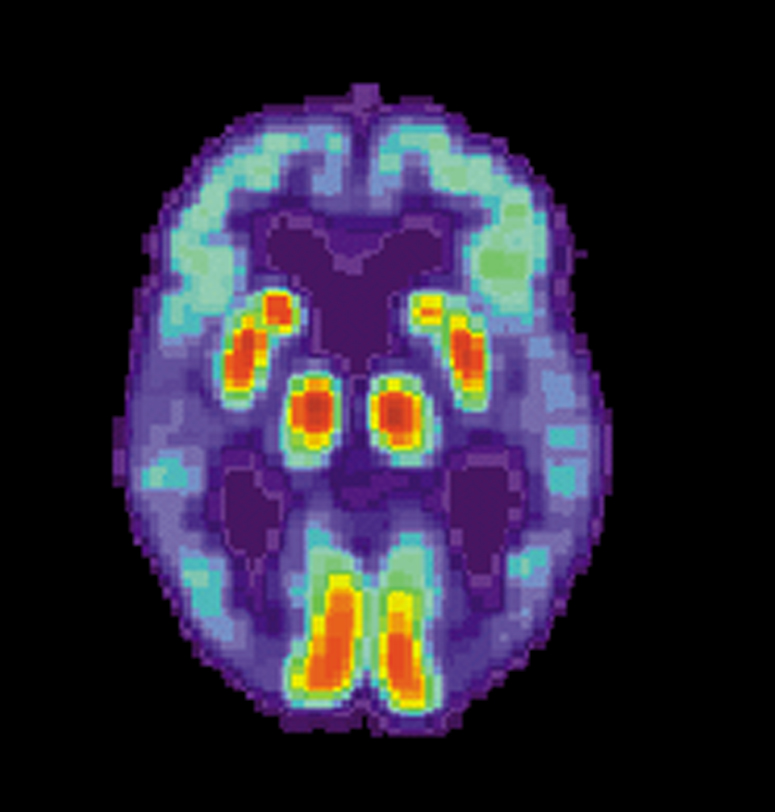

Alzheimer’s Disease

Alzheimer’s disease is a degenerative condition of the brain, specifically the cortex.